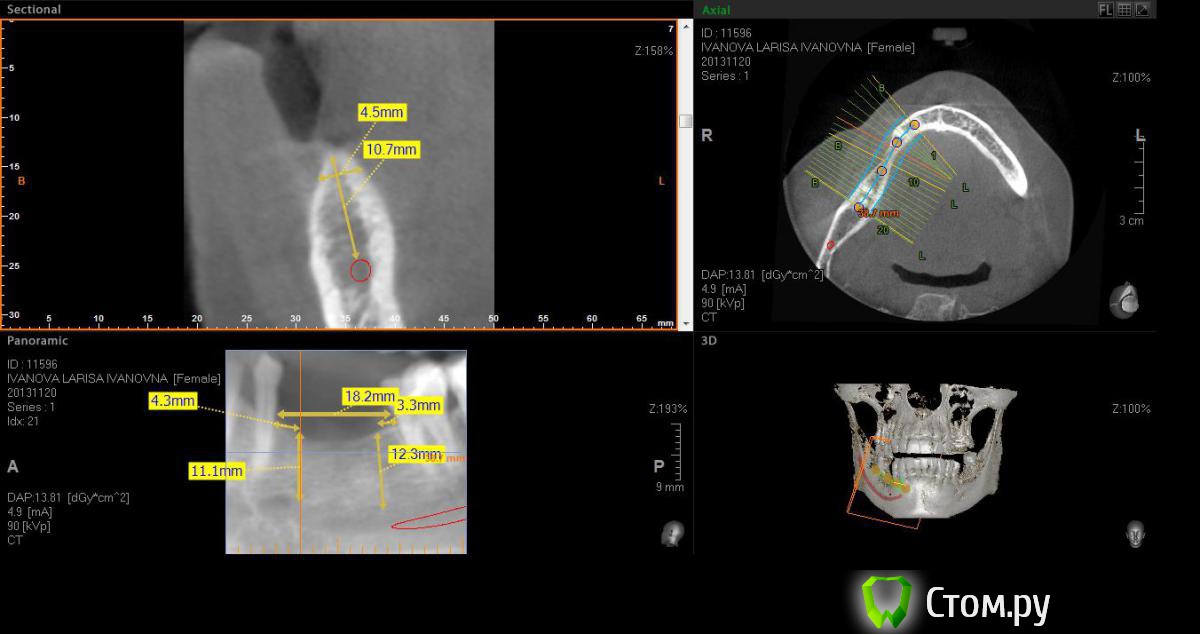

Neilrus Опубликовано 2 марта, 2014 Поделиться Опубликовано 2 марта, 2014 (изменено) Здравствуйте, коллеги, уделите 6 минут новичку…у меня тут проблема, она абсолютно не проблема для того, кто хоть пару раз делал расщепление гребня,а я вот только курсы закончил и у меня планируется через 7 дней операция. Вроде все понял, но пока стремаюсь.Посморите снимки, пожалуйста, а я напишу тот протокол, который хочу применить, как на курсах понял, поправьте, если что не так )) Спросил бы у лектора, но ведь так всегда, да?)Планирую иплантаты по месту 45,46 зубов.Гребень узкий в обл 45 з и близко нч нерв, как раз поднимается к ментальному отвертстию. С этим и связан страх. Никаких транспозиций делать пока не готов. В арсенале нет пьезотома пока, вот пару таких операций сделаю и куплю.Планирую поставить 4,2*8 для 45 зуба и 4,2*11,5 для 46 зуба (Мis Seven) . Соединю коронки, т.к. премоляр коротковат. Итак, план по захвату таков:1)Разрез чуть язычнее середины гребня, откидываем слиз-надк лоскут с аккуратностью в области менталиса.2)По центру гребня делаем горизонтальный распил сепарационным диском диаметром 7 не доходя до зубов по 3 мм. Глубина распила получается 3,3. Потом беру диск 10 и глубина уже 4,8.3)Мелким 7мм диском делаю дистально вертикальный распил на глубину 3,3 длиной с длину имплантата моляра 11,5, а медиально тем же диском на длину 4-5 мм, ниже страшно, боюсь нерв задеть. На верхушке гребня соединяем распилы (черные линии на моем рисунке). Делаем бором твердосплавным шаром компактостеотомию в преполагаемом месте перелома.4)Берем долото и вставляем в горизонтальный разрез и постукиваниями молоточка продвигаем его на глубину до 8мм по всей длине разреза (длина миниального импланта). Чуть покачивая из стороны в сторону, при этом убирая закругления от диска внутри горизонтального распила. (На рисунке, который сам нарисовал – это красная зона).5)Немного раздвинув края в месте предполагаемых имплантатов пилотом 2мм прохожу на глубину имплантатов. Проверяем параллельность.6)Загоняю по очереди мисовские компрессионные винты на глубину имплантатов до диаметра третьего винта 2,4- 3,7 (т.к. импланты 4,2)7)Теперь они вроде как должны быть нормально раздвинуты ( здесь я не понял, нужно проходить фрезами из хир набора или так хорошо войдут) Может финишной фрезой пройти хотя бы на всю глубину имплантатов? Подскажите, пожалуйста.8)Дальше заполняю пустоты MP3, фиксирую пинами MCT 2.75 мембрану evolution толстую на 2 мм ниже коспактостеотомии, перекидываю на язычную сторону под надкостницу краешек запихиваю.9)Мобилизую лоскут, ушиваю все наглухо и надеюсь на лучшее. ВОПРОСЫ:1)не коротковат ли имплант 4,2*8, но ведь я соединю их? Можно немного наклонить его медиально, выход шахты оставить там же, но апикальную часть ближе к моляру, тогда длина 10 выйдет, но там и так не получается соостно с зубами имплант размстить, а тут его и такая ангуляция, не хорошо, я думаю.2)Отслойка лоскута медиально- правильно я написал или порвется тогда и лучше рассечь связку на 44 и медиально вниз.3)Фрезы хирургические нужно использовать при нормальном раздвигании краев гребня? Кстати, нормально-это сколько для диаметра имплантата 4,24)Язычно нужно как-то дополнительно фиксировать мембрану?5)MP3 мешать с аутокостью и кровью из ловушки?6)Как лоскут мобилизовать медиально рядом с ментальным нервом? Пластика зкпд будет одновременно с открытием.Спасибо вам за ваше время ) Изменено 8 мая, 2014 пользователем Bier Ссылка на комментарий